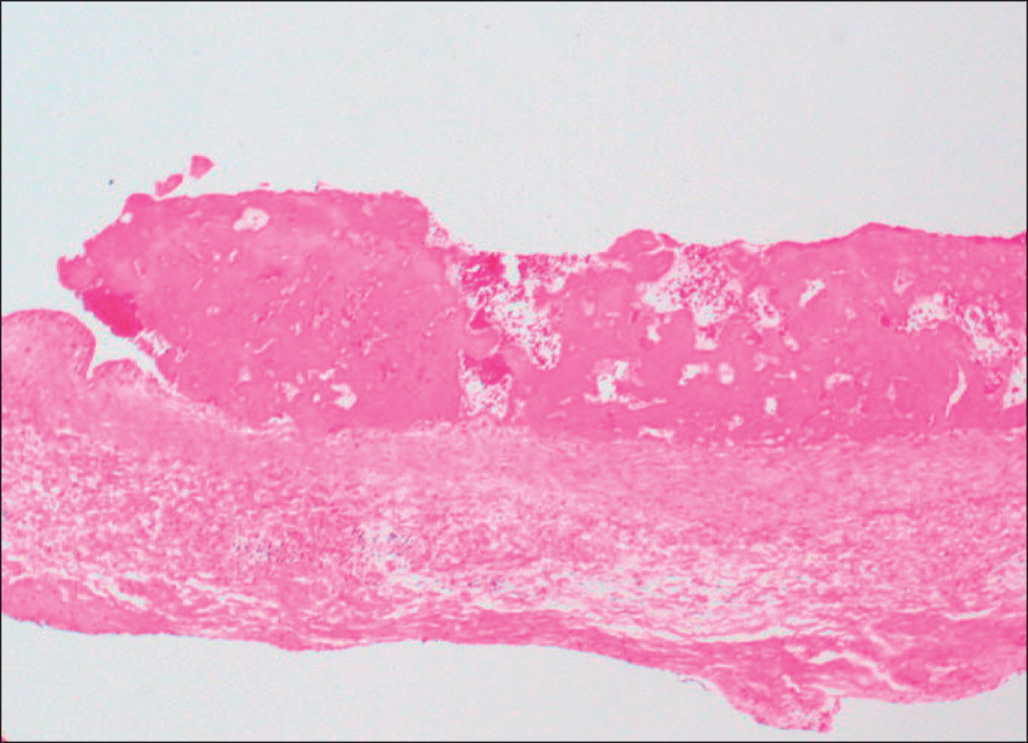

It is important to assess the presence and extent of infection within the burn wound, both by careful clinical examination of wounds and by biopsy of suspicious areas. A high index of suspicion serves the burn patient well. All biopsy and excision specimens in our institution are sampled and studied histologically with special stains (a tissue Gram stain for bacteria and methenamine silver for fungi). In large excision specimens, samples are taken from sites of especially deep tissue injury and sites that show abnormal discoloration of dermal or subcutaneous tissue. When infectious microorganisms are found, it is important to determine their location with respect to the boundary between living and necrotic tissue. This boundary may be irregular, but it is generally distinct and marked by inflammation in wounds several days old, but may be indistinct in very fresh specimens, as karyolysis takes some time to develop in burn wounds. Wound infections generally begin with colonization of the skin surface and proliferation of organisms on the surface, often with extension into hair follicles, followed by growth within the necrotic tissue. Both the coagulum on the surface and the necrotic epidermis and dermis are considered part of the burn eschar. Growth within necrotic tissue is considered evidence of invasion of necrotic tissue, however, and potentially more dangerous than growth on the surface of necrotic skin, under a layer of fibrin, and debris. Even when quantitative cultures show more than 10 5 bacteria per gram of tissue, when careful histologic study shows that the organisms are limited to the skin surface or the superficial necrotic tissue, the risk of sepsis appears to be low. Such growth on or in necrotic tissue, however, sets the stage for invasion of viable tissue. The finding of clusters of bacteria or fungi within viable tissue implies a serious risk of sepsis and further tissue invasion. Bacterial invasion of viable tissue is readily apparent by histologic study of appropriate tissue samples ( Fig. 38.1 ). Invasive fungal infection presents a somewhat different pattern, in that there is often a wavefront of necrosis that accompanies fungal invasion ( Fig. 38.2 ). Thus the presence of fungal hyphae extending to a boundary between necrotic and viable tissue is considered evidence of fungal invasion of viable tissue. On this basis, infections identified within burn wounds are reported as surface colonization, invasion of necrotic tissue, which may be superficial or deep, and invasion of viable tissue. The responsible surgeon is called immediately when invasion of viable tissue is found. Diagnosis of viral infection of the skin is achieved most efficiently by sampling freshly opened vesicular lesions or the bases of recently ruptured vesicles, and molecular testing by polymerase chain reaction (PCR).

This micrograph shows fungal hyphae within necrotic tissue extending close to the boundary with intact, viable dermal tissue. Periodic acid–Schiff stain.